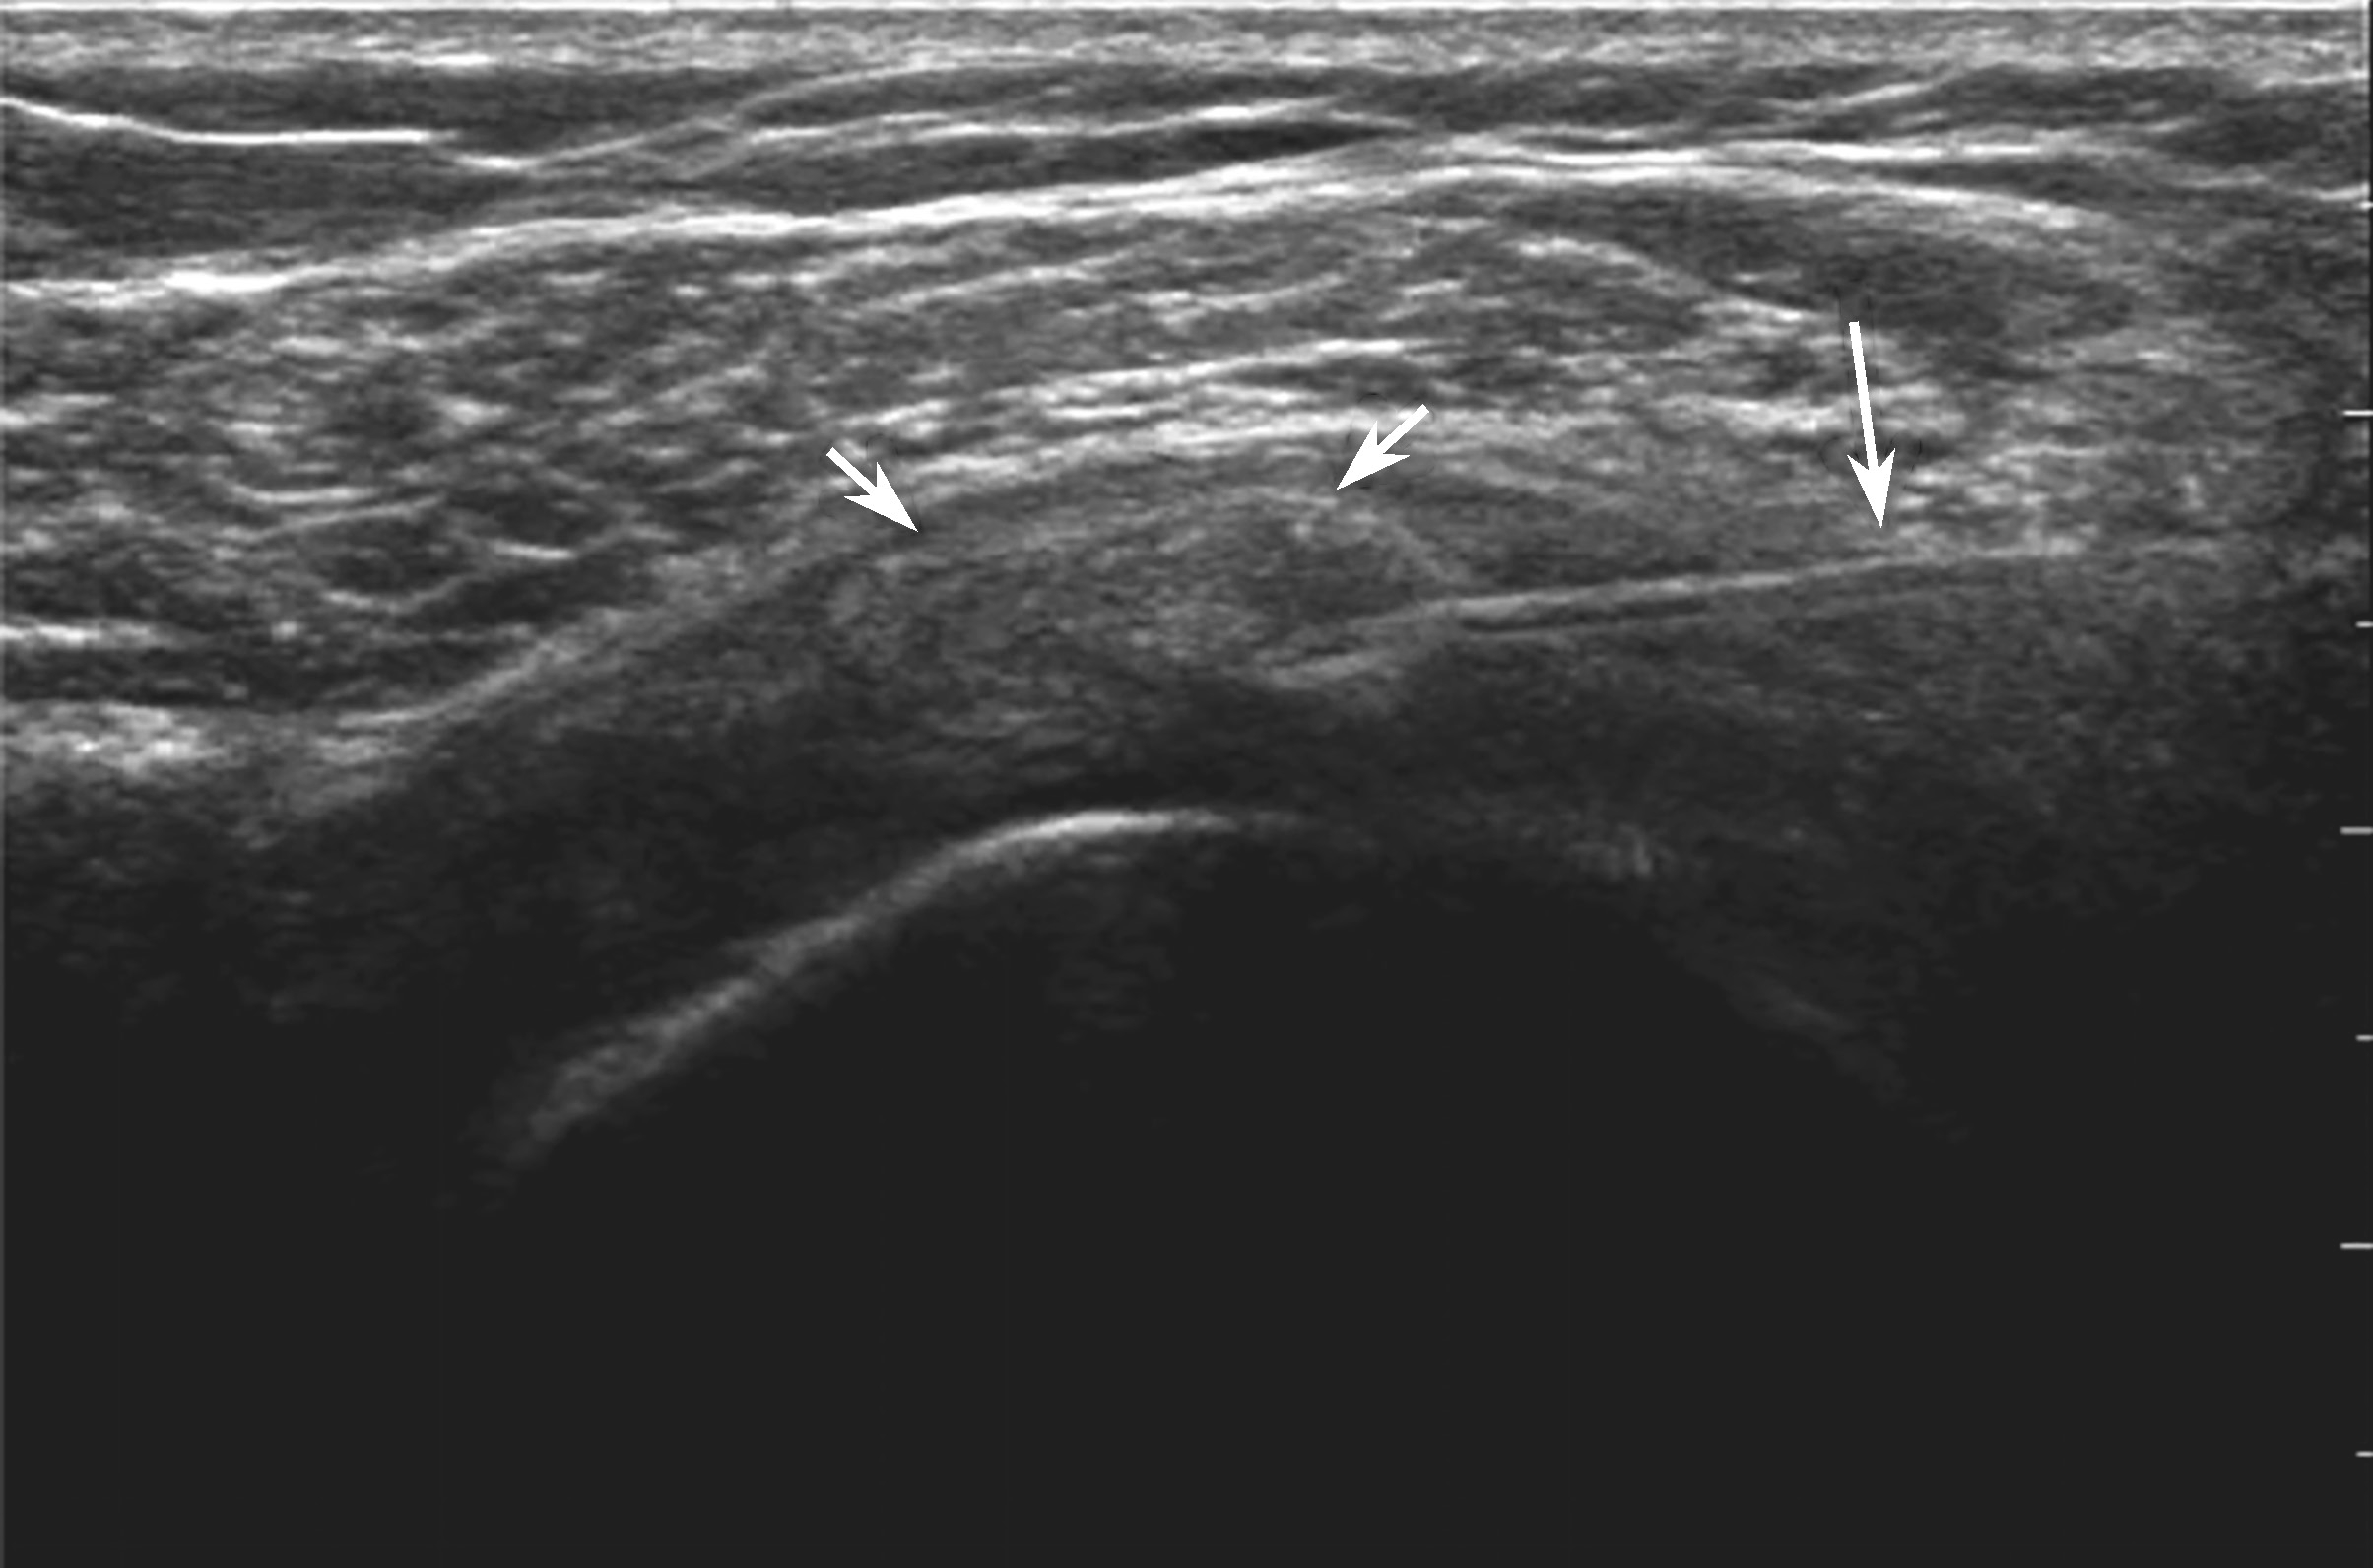

对物理治疗和口服药物治疗无效的钙化性肌腱炎,可行超声引导下钙化灶冲洗抽吸治疗,缓解疼痛和改善患者的活动功能。吸收期的钙化灶往往无明显声影,呈弱回声或稍强回声(图 2-2-1)。

▲ 图2-2-1 钙化性肌腱炎超声图

星号:钙化灶;箭头:肩峰下-三角肌下滑囊;Del:三角肌;SUP:冈上肌腱;HH:肱骨头